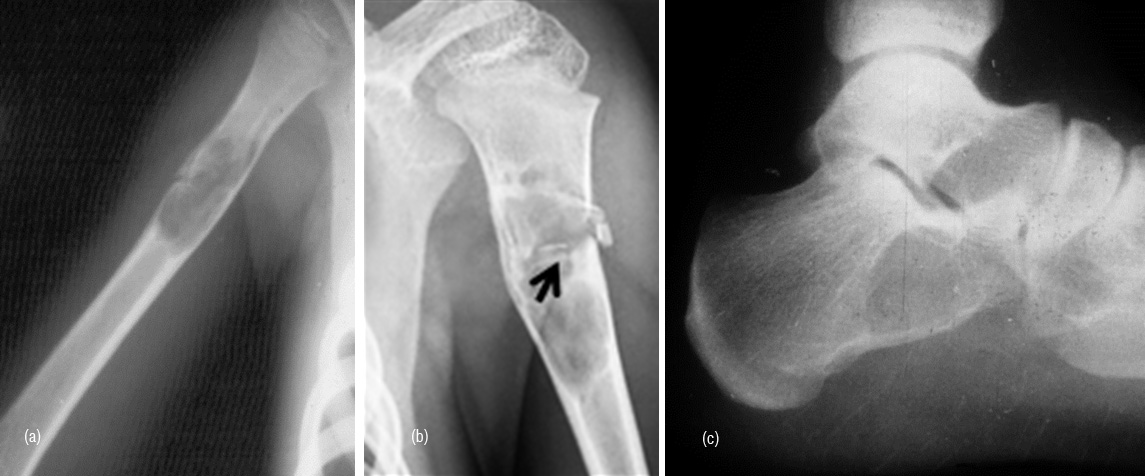

Bone infarcts

Old healed infarcts in the metaphyseal region of long bones simulate enchondroma. However, the radiological findings of an elongated lesion with serpentine calcifications and the peripherial fibroosseious membrane differentiates it from enchondroma (Figure 18abc). Occasionally the appearance may be similar to osteosarcoma (Figure 18d).

Figure 18: (a) Enchondroma, (b) Calcified infarct, (c) Calcified infarct in lateral view, (d) Osteosarcoma simulating infarct.

Intraosseous ganglion

It is a subarticular lytic lesion containing synovial fluid and is often associated with degenerative joint disease. It is encountered in the proximal and distal ends of tibia. Medial malleolus is common site (Figure 19).

Figure 19: Intraosseous ganglion in the medial condyle of tibia.